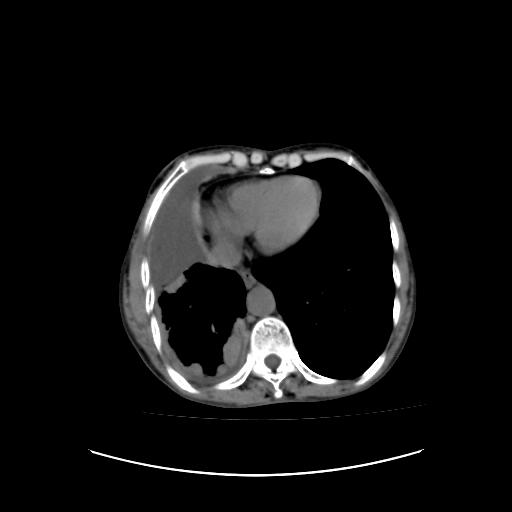

标题: CT16930:女 59 胸痛6个月 胸水脱落细胞学见瘤细胞 [打印本页]

标题: CT16930:女 59 胸痛6个月 胸水脱落细胞学见瘤细胞

可见多发肺内病灶,且胸膜病灶较多有圆球状而非丘状,多考虑胸膜转移瘤伴胸腔积液,右侧胸廓缩小固定,且部分病灶呈丘状,尚不除外恶性胸膜间皮瘤伴肺内转移

恶性胸膜间皮瘤伴肺内转移可能性大;或胸膜、肺内均为转移瘤,左肺下叶亦见多发小结节影。

右侧胸廓塌陷,右侧胸膜广泛增厚并见多发胸膜结节,右侧少量胸腔积液并包裹。

胸膜转移瘤  包裹性胸腔积液  肺内转移

右胸腔结节均考虑来自胸膜(部分来源于叶裂),考虑胸膜间皮瘤或转移瘤.